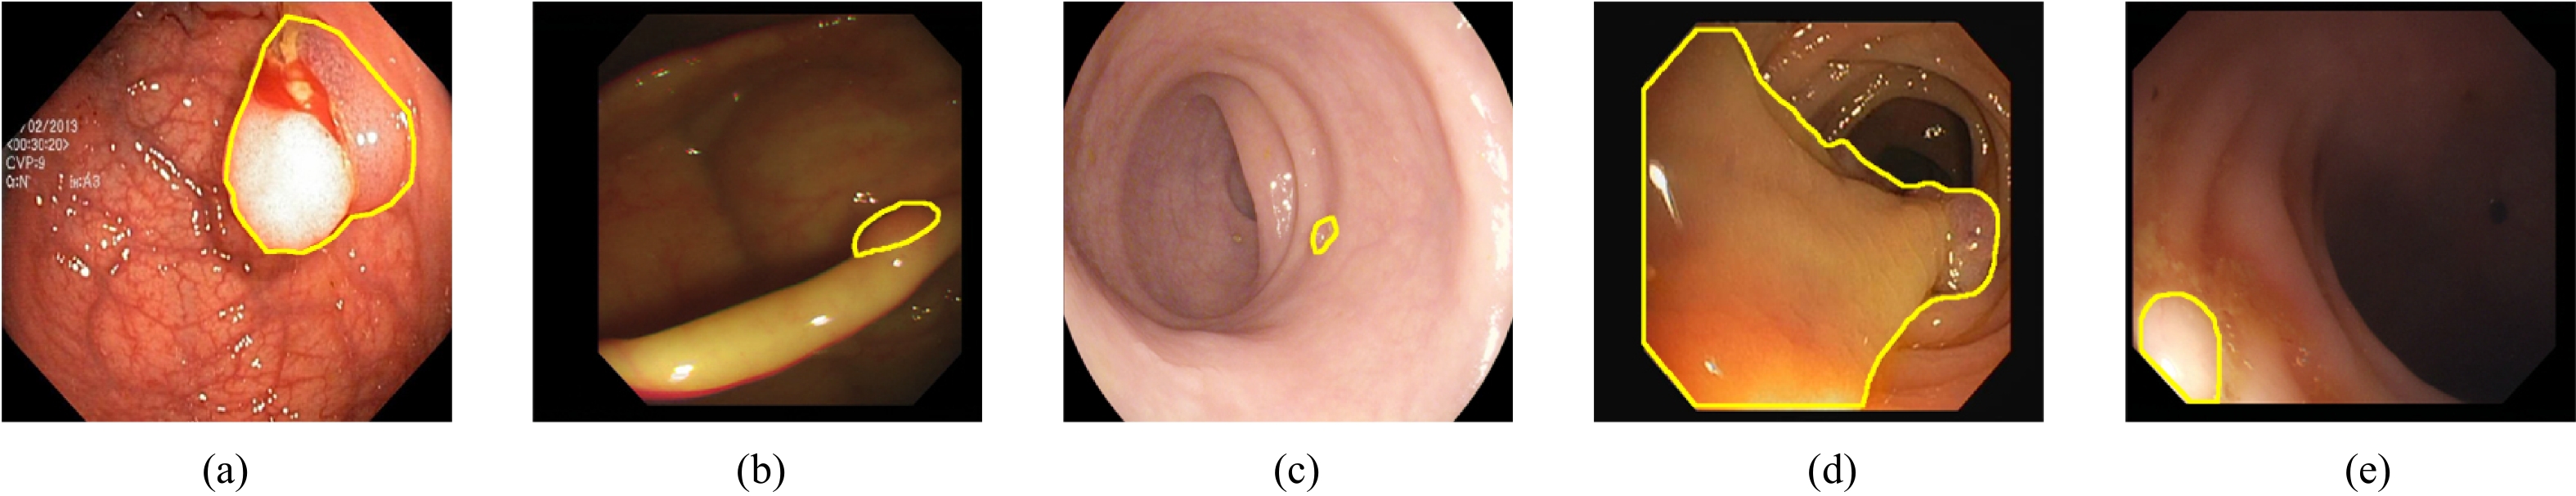

MFAINet: Multi-Receptive Field Feature Fusion With Attention-Integrated for Polyp Segmentation

Guangzu Lv, Bin Wang, Cunlu Xu, Weiping Ding, Jun Liu

2026, 13(4): 822-836. doi: 10.1109/JAS.2025.125408

Abstract(1364) HTML (87) PDF(70)

Abstract:

Colorectal cancer has become a global public health concern. Removing polyps before they become malignant can effectively prevent the onset of colorectal cancer. Currently, multi-receptive field feature extraction and attention mechanisms have achieved significant success in polyp segmentation. However, how to effectively fuse these mechanisms and fully leverage their respective strengths remains an open problem. In this paper, we propose a polyp segmentation network, MFAINet. We design an attention-integrated multi-receptive field feature extraction module (AMFE), which uses layering and multiple weightings to fuse the multi-receptive field feature extraction and attention mechanisms, maximizing the extraction of both global and detailed information from the image. To ensure that the input to AMFE contains richer target feature information, we introduce a multi-layer progressive fusion module (MPF). MPF progressively merges features at each layer, fully integrating contextual information. Finally, we employ the selective fusion module (SFM) to combine the high-level features produced by AMFE, resulting in an accurate polyp segmentation map. To evaluate the learning and generalization capabilities of MFAINet, we conduct experiments on five widely-used public polyp datasets using four evaluation metrics. Notably, our model achieves the best results in nearly all cases.